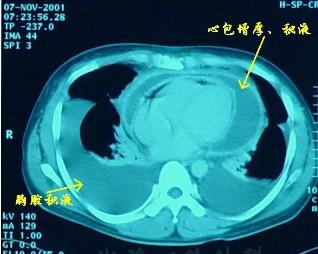

• 心包炎

628健康網為您分享有關心包炎的癥狀,心包炎的治療方法,心包炎的預防知識,心包炎的癥狀圖片,心包炎吃什么藥,心包炎怎么治...